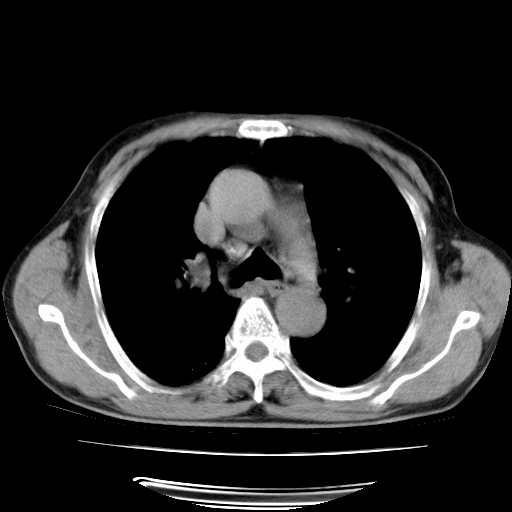

男,71岁,咳嗽,气喘10年,再发并咯血.胸片见气胸

考虑  左肺中心型肺癌伴阻塞性肺炎,肺不张,纵膈淋巴结肿大。慢支炎,肺气肿,左侧气胸肺压缩5%

左侧中央型肺癌伴纵膈淋巴结转移。

左肺中心型肺癌伴阻塞性肺炎,肺不张,纵膈淋巴结肿大

1)考虑左肺中心型肺癌伴阻塞性肺炎、左肺下叶肺不张、左侧肺气肿,纵膈淋巴结转移。2)左侧气胸(肺组织压缩约5%)。

左肺中心型肺癌伴阻塞性肺不张、肺气肿 。

1)考虑左肺中心型肺癌伴阻塞性肺炎、左肺下叶肺不张、左侧肺气肿,纵膈淋巴结转移。2)左侧气胸。